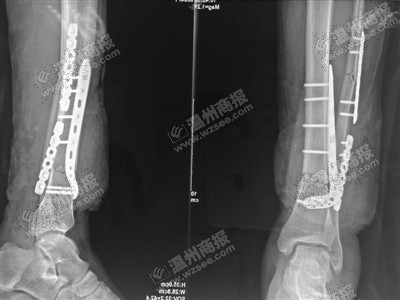

X光显示鲍成远右小腿完全被勒断。医院供图金鱼翻拍

因他自救得当,目前断肢已接上。医院供图金鱼翻拍

刘斌告诉记者,在缆绳巨大作用力下,鲍成远右小腿伤口周围皮肤被挤压变形,近端皮肤缺损,胫骨粉碎性骨折,腓骨多段骨折。

手术过程中,他们对鲍成远伤口处一些挫烂后无生机、无活力的软组织进行剪除。然后,通过锁钉螺钉对骨折部位进行固定,接着,从身体其他部位移植肌腱、血管等,在显微镜下,对右小腿缺损的肌腱、血管等处进行缝接。经过10余小时手术,鲍成远的断腿终于成功接回。